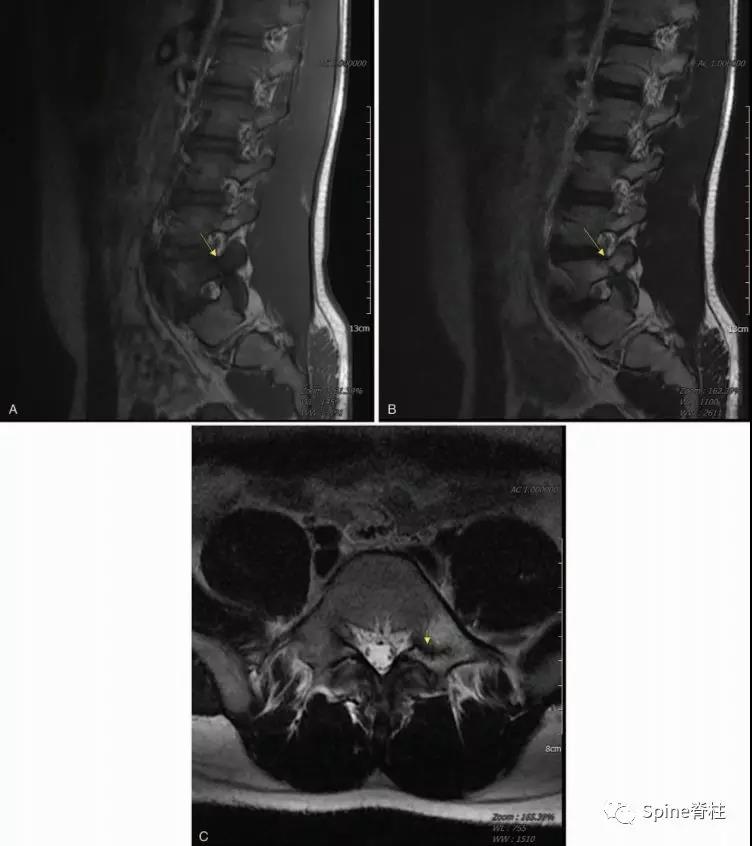

图:15岁腰痛男孩,左侧腰5椎弓根裂A:T1左侧腰5椎弓根低信号(箭头);B:T2左侧腰5椎弓根高信号(箭头);C:T2轴位左侧腰5椎弓根骨折线明显,伴高信号区(箭头)